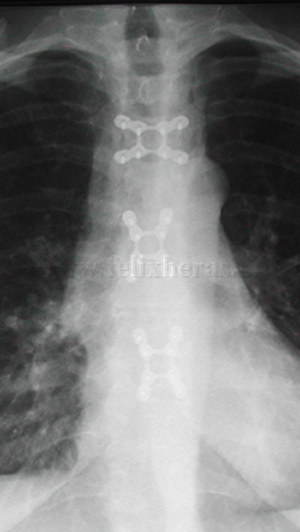

Osteosíntesis esternal